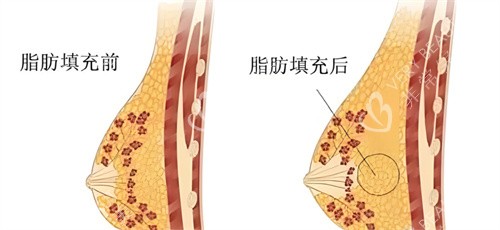

自体脂肪隆胸手术完成两年后,移植的脂肪已经基本稳定,但这不意味着可以完全放松警惕。本文将为您详细介绍术后两年的注意事项、潜在风险以及如何通过科学护理维持理想结果。

手术两年后,脂肪存活率已基本稳定。此时,成功存活的脂肪细胞会像身体其他部位的脂肪一样,随着体重的增减而变化。如果体重增加,胸部可能也会相应变大;如果体重减轻,胸部尺寸则可能缩小。

正常情况下,术后两年的乳房形态应该较为自然,手感柔软。但需注意,脂肪吸收不均匀可能导致局部硬结或轻微不对称,若问题明显,可考虑***医生是否需要修复。